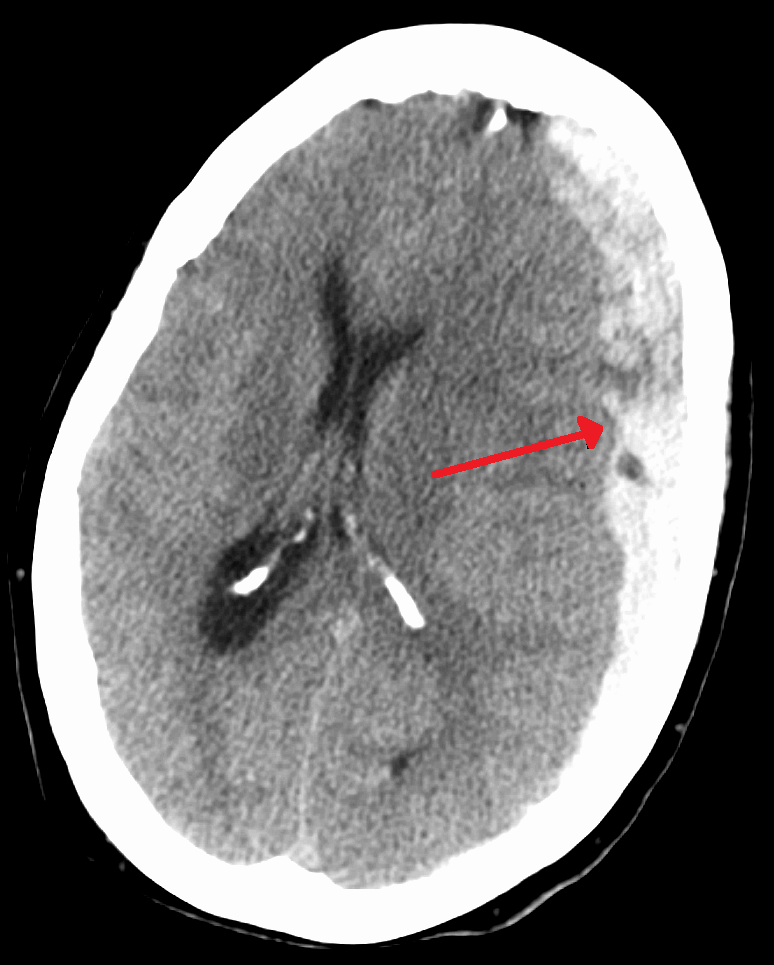

Herniation

The displacement of brain tissue as a result of a force or higher intracranial pressure is known as herniation.

The most frequent type of intracranial herniation is a subfalcine herniation.

In subfalcine herniation the brain tissue protrudes through the falx cerebri.